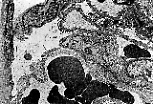

Observation au M.E.T.

Sur cette micrographie, s'observent une cellule pavimenteuse du feuillet pariétal, la chambre glomérulaire ainsi que deux podocytes dont les pédicelles s'appliquent intimement sur les membranes basales de trois capillaires fenêtrés.

La filtration se réalise depuis les vaisseaux sanguins vers la chambre glomérulaire au travers de la membrane de filtration glomérulaire.

Cette vue permet d'illustrer les structures au travers desquelles se réalise la filtration glomérulaire, à savoir :

- les pores endothéliaux,

- la lame basale,

- les fentes épithéliales entre les pédicelles des podocytes.

La membrane basale des capillaires glomérulaires est épaisse; elle est subdivisée en trois couches :

- la lamina rara interna accolée à l' endothélium fenêtré ,

- la lamina densa,

- la lamina rara externa sur laquelle s'appliquent les pédicelles podocytaires.

Les fentes de filtration sont partiellement occupées par une membrane appelée la slit membrane ou membrane de la fente de filtration.

Cette autre micrographie électronique prise au M.E.T. montre une cellule mésangiale. Son cytoplasme s'applique directement sur l'endothélium du capillaire fenêtré sous-jacent.